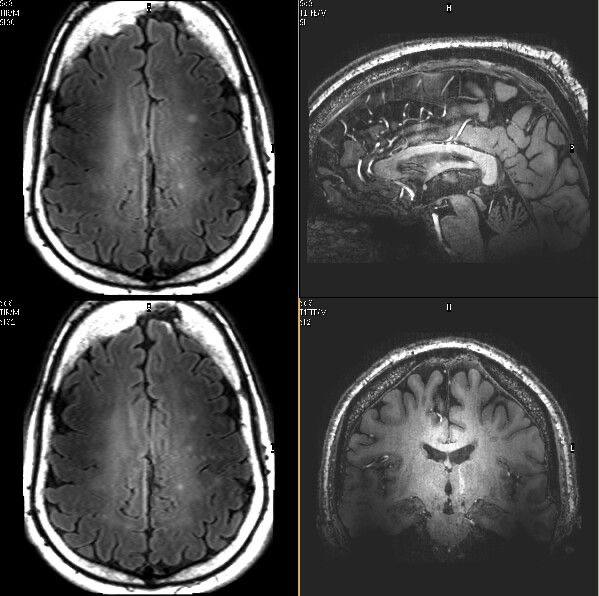

В ходе специальных исследований добровольцев помещали в томограф и предлагали решать простые логические задачи - нажать кнопку, выбрать вариант ответа, принять элементарное решение.

Томограф фиксировал активность мозга за несколько секунд до того, как человек осознавал свой выбор и озвучивал ответ.